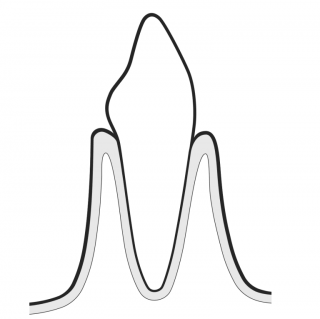

PRESERVE HEALTHY TEETH

GBT minimizes the use of power and hand instrumentation. AIRFLOW® is minimally invasive on all types of dental tissues: dentine, cementum, enamel and gums. Minimal abrasion for maximum comfort: GBT enables the patient to enjoy natural teeth and implants for much longer.